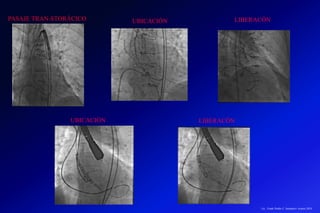

UBICACIÓN

LIBERACÓN

PASAJE TRAN-STORÁCICO

El desarrollo de los TCMD ha permitido realizar una serie de procedimientos a

nivel cardiovascular (angiografía cardiaca, aortica y sistema vascular periférico.)

que permiten realizar en la salas de hemodinámicas procedimientos como

remplazo de la válvula aortica, colocación de stents por aneurismas o disección

de la aorta.